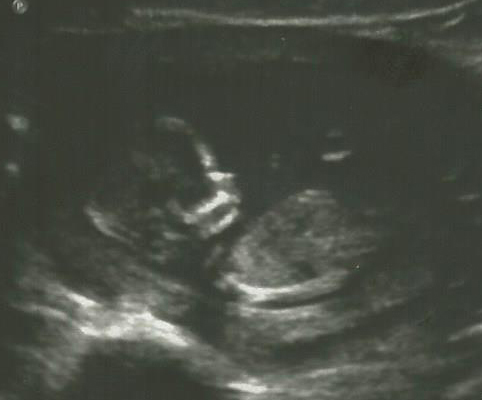

I'm driving myself crazy! We didn't get a nub shot, but any guesses based on the skull (even though I know it's an unproven theory)